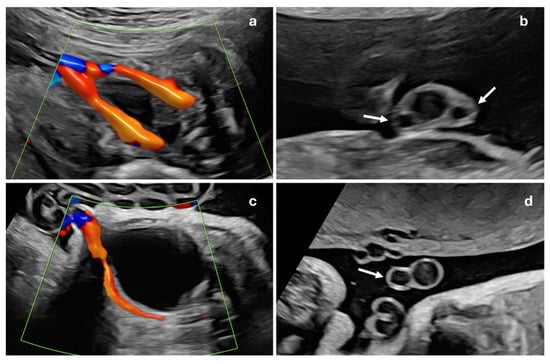

A prenatal examination of the umbilical cord is an essential part of the ultrasound scan in pregnancy. The presence of a single artery, known as a single umbilical artery (SUA) (Figure 1), is considered a risk marker for trisomy and may be associated with fetal malformations in up to 11–30% of cases [1,2,3]. When a single umbilical artery is observed without any other detectable malformations, it is termed isolated single umbilical artery (ISUA). The findings in existing studies are inconsistent: some studies report that the presence of SUA is linked to an increased risk of preterm birth and fetal growth restriction (FGR) and higher perinatal morbidity and mortality [2,4,5,6,7,8]. However, these associations have not been corroborated by other research [9,10], leading to conflicting conclusions regarding the implications of SUA.

This is a descriptive, observational and retrospective study with a total of 1157 consecutive singleton pregnant patients treated at the Department of Gynaecology and Obstetrics of the Hospital Universitario de Salamanca, during the period from 1 January to 31 August 2023. Inclusion criteria were women with singleton gestations without other associated ultrasound markers, nuchal translucency less than 3.5 mm and no fetal malformations. Exclusion criteria were multiple gestations or those that did not meet the inclusion criteria. These pregnancies were compared with 77 gestations with ISUA, whose data were collected during the years 2019 to 2023 at the same center, ISUA being defined as the presence of a single umbilical artery without any other ultrasound signs or markers or fetal malformations (Figure 2). All ultrasound examinations were performed by one of the five specialists belonging to the Prenatal Diagnosis Department at the 20th-week ultrasound scan (AMC, MOMR, PO, AVY, FJG), following the ISUOG Protocol for the performance of the routine mid-trimester fetal ultrasound scan [11]. Once ISUA was diagnosed, it was confirmed by another of these specialists in the department at a subsequent visit. This study was approved by the Hospital Ethics Committee. Considering that this was a retrospective study, no informed consent was needed from the patients to carry out this study. Sample size was calculated using the WinEpi calculator (http://www.winepi.net/f102.php, accessed on 1 June 2022), considering a prevalence of 1% for ISUA [8] with a confidence level of 95%. Data were collected in a database created specifically for this study with Microsoft Excel (Microsoft Corporation, Redmond, WA, USA), which was accessible from the outpatient clinic, the delivery room and the hospital ward.

Figure 1. Prenatal ultrasound examination of the umbilical cord. Normal fetal umbilical cord in color Doppler mode (a), showing two umbilical arteries passing on either side of fetal bladder, and in grayscale transverse section (b), where two umbilical arteries (white arrows) and umbilical vein are visible, confirming three-vessel cord. Fetal umbilical cord with single umbilical artery in color Doppler mode (c), demonstrating only one umbilical artery adjacent to fetal bladder, and in grayscale transverse section (d), showing single artery (white arrow) and one umbilical vein, indicating two-vessel cord.